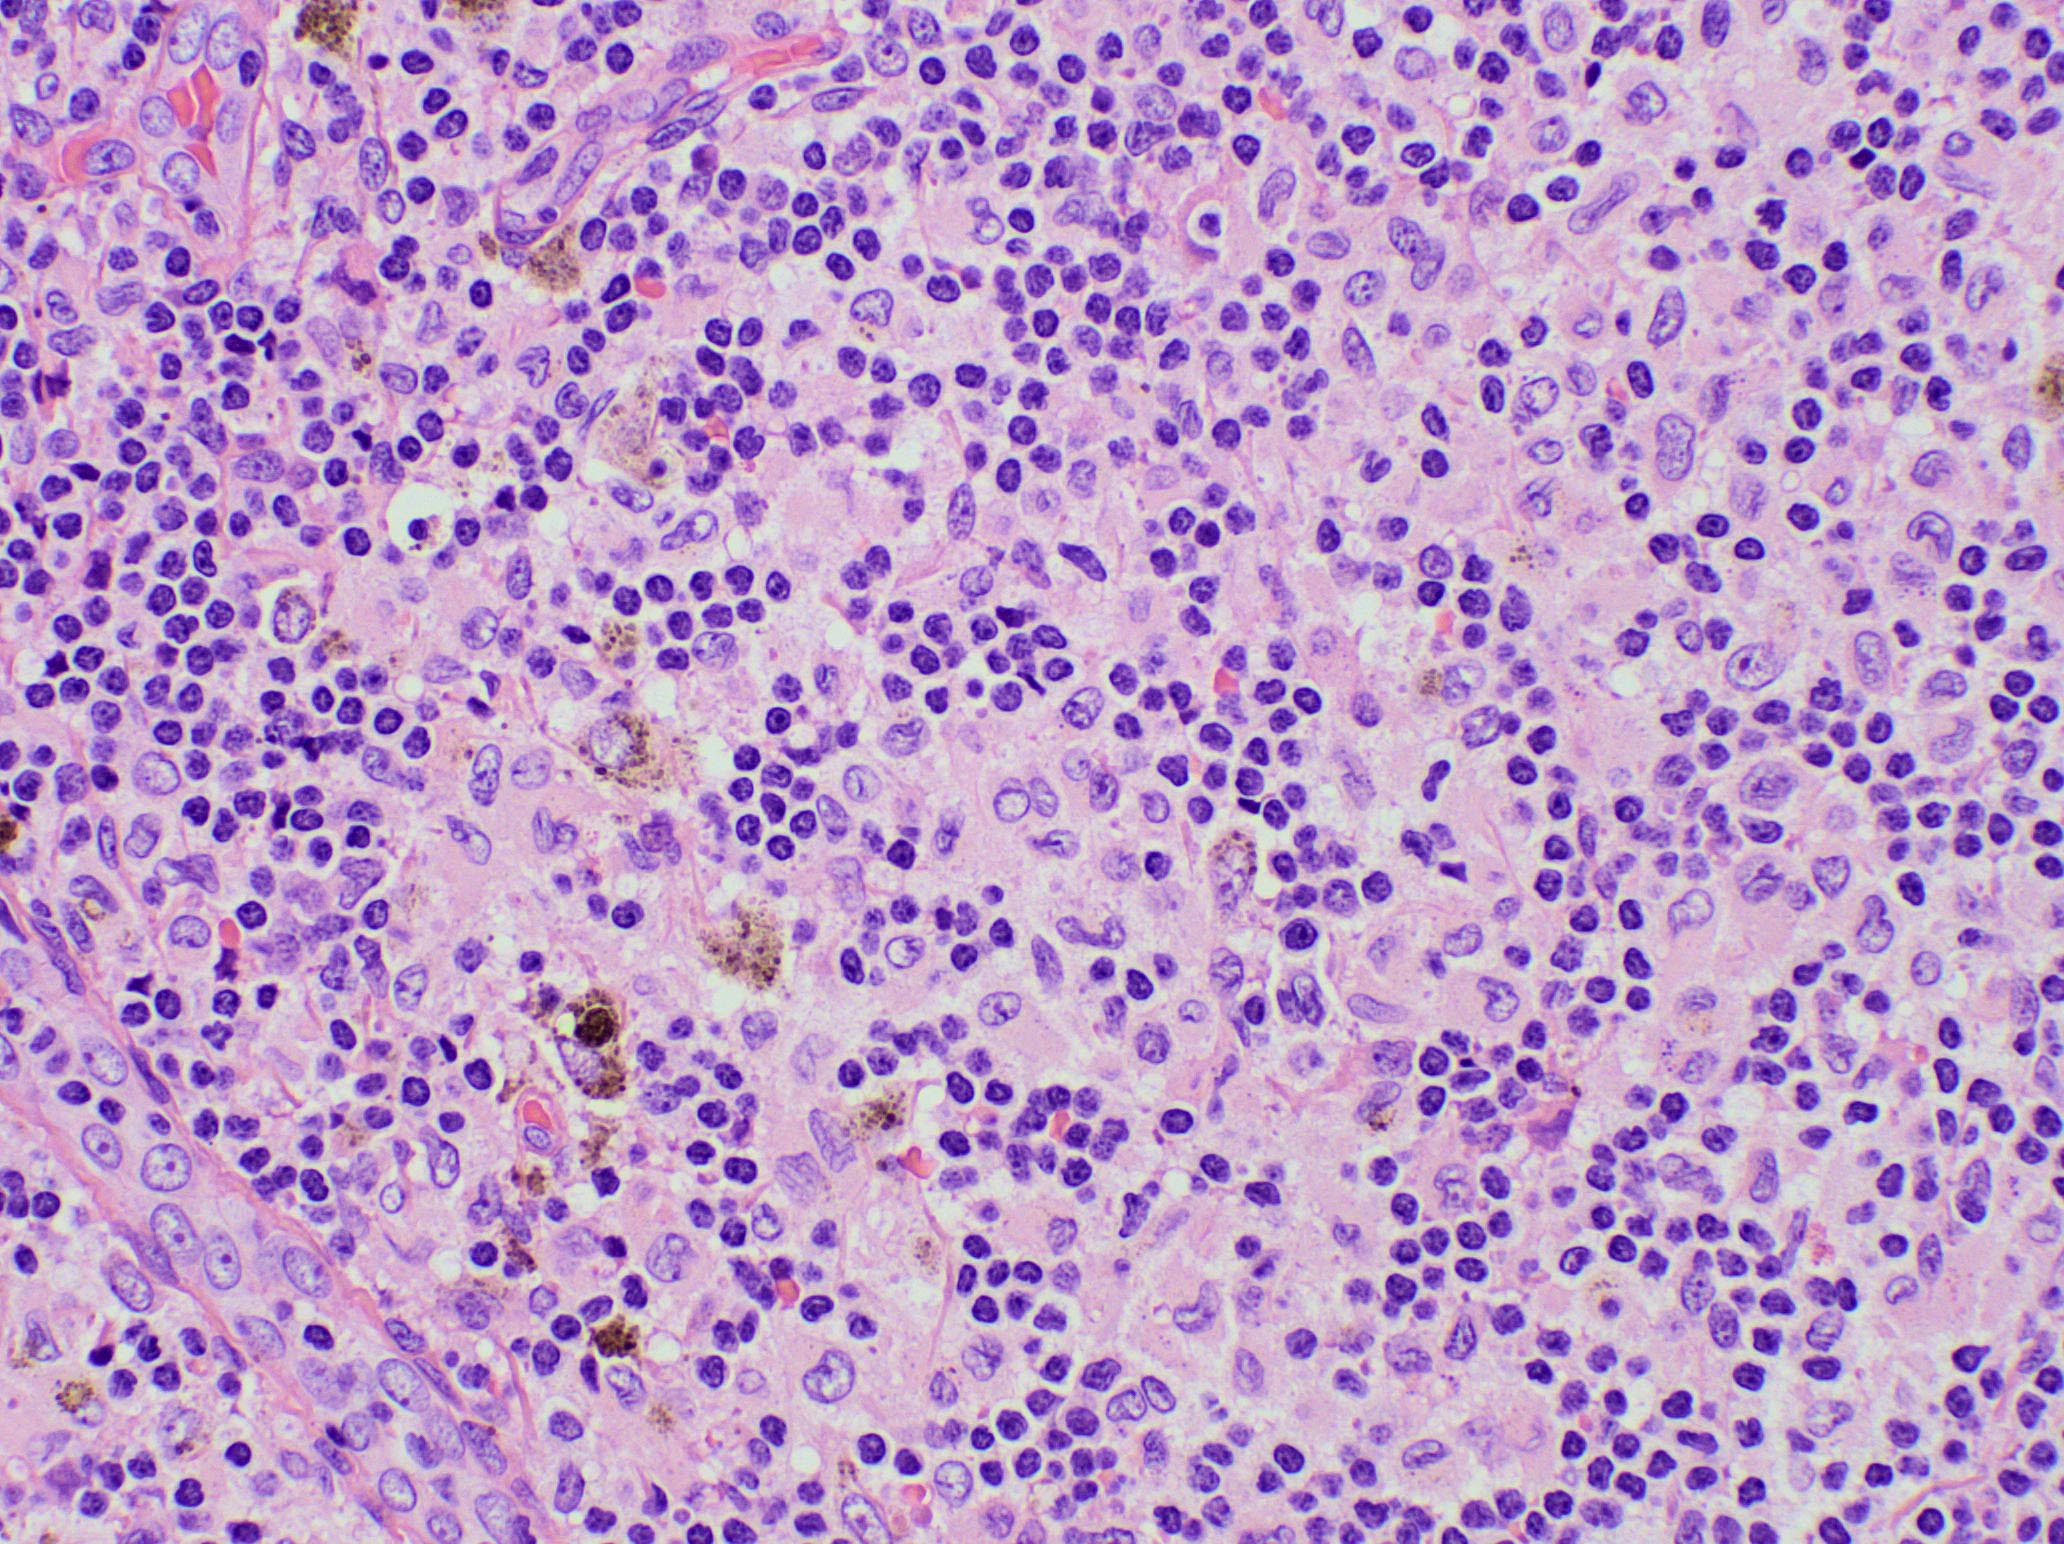

Microscopic (histologic) images

Contributed by Ingrid Tam, M.D., M.Sc., Emina Emilia Torlakovic, M.D., Ph.D. and Nikhil Sangle, M.D. (Case #396)

- Spectrum of changes from mild to severe, characterized by paracortical expansion with pale, irregularly shaped areas containing numerous pale staining histiocytes, interdigitating dendritic cells, Langerhans cells and occasional immunoblasts

- Predominance of interdigitating dendritic cells over Langerhans cells, which are indistinguishable on morphology alone

- Both cell types show ill defined cell borders with fine irregular reniform nuclear contours and occasional nuclear grooves

- Paracortical or sinusoidal histiocytes and macrophages often contain cytoplasmic melanin pigment but they also can contain hemosiderin or lipid